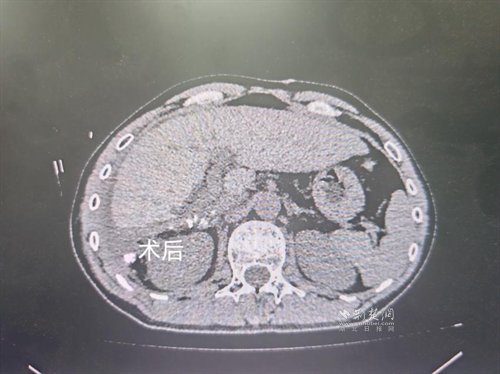

經(jīng)過肝膽外科牽頭組織的多學(xué)科MDT會診,團(tuán)隊確認(rèn)其適合接受當(dāng)前國際先進(jìn)的釔90樹脂微球選擇性內(nèi)放射治療。治療僅一個月后,患者病灶即從10cm縮小至6cm;術(shù)后六個月復(fù)查顯示,病灶體積進(jìn)一步縮小近40%,影像學(xué)檢查提示完全緩解,臨床分期成功轉(zhuǎn)化,達(dá)到手術(shù)切除標(biāo)準(zhǔn)。